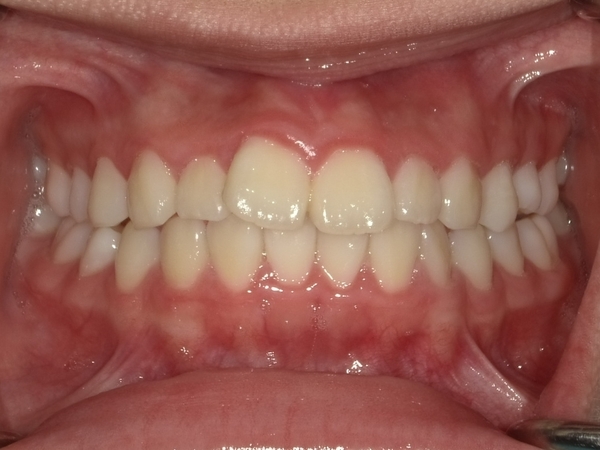

〇ご相談内容:歯のねじれが少し気になる〇矯正の種類:マウスピース型矯正「インビザライン」〇治療期間:14週間〇治療費用:44万円(税込)